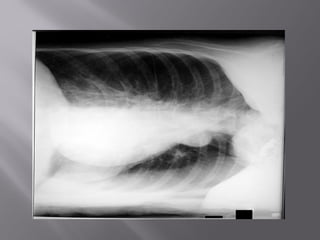

 6. Inspiration

 Should be able to

count 9-10 posterior

ribs

 Heart shadow should

not be hidden by the

diaphragm

9-10 posterior ribs are

9

About 8 posterior ribs are

showing

8

With better inspiration,

the “disease process” at

the lung bases has

cleared

 6. Inspiration Should be able to count 9-10 posterior ribs  Heart shadow should not be hidden by the diaphragm 1 2 3 4 5 6 7 8 9 10

9-10 posterior ribsare 9 About 8 posterior ribs are showing 8 With better inspiration, the “disease process” at the lung bases has cleared